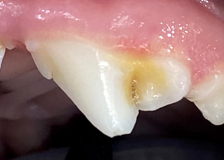

스케일링 전후 사진

스케일링 전

스케일링 후